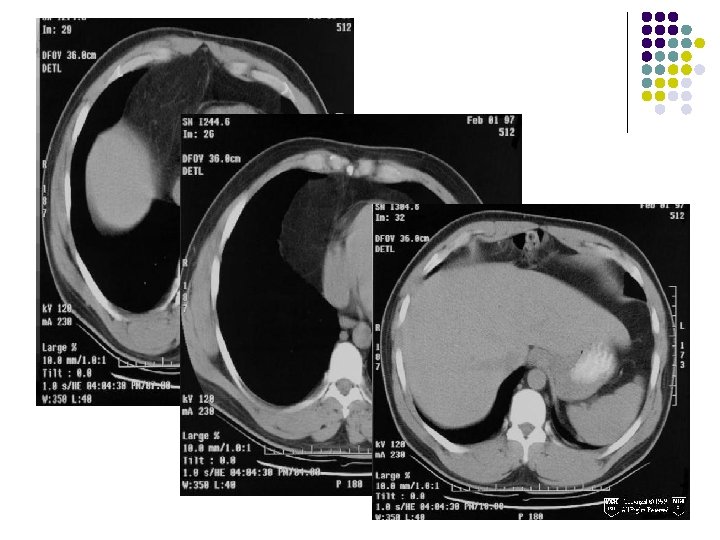

CHEST X-RAY: l A large smooth bordered opacity projecting in the right cardiophrenic angle. l Vessels and the right heart border can be seen through the opacity, which may be of fat density.

CT FINDINGS: l A large amount of fat density adjacent to the right heart border which contains multiple small vessels and is in continuity with abdominal fat in the mesentery. l A portion of the transverse colon lies within the inferior portion. l There is no evidence of bowel obstruction